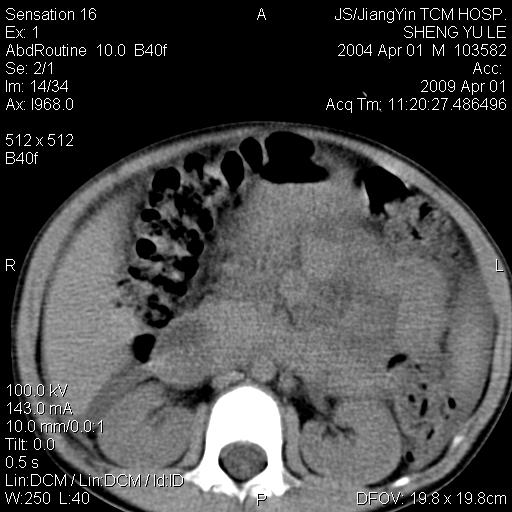

m,5岁。尿痛尿频数天。既往无病史。ct平扫腹盆腔积液。膀胱壁明显增厚。另可见心包增厚。wbc5万,骨髓穿等结果。请指教。

膀胱影像表现结合临床应该是急性膀胱炎症,但为什么有腹水呢?双肾输尿管无扩张,泌尿系压力应该不大不至于引起尿外渗,应该是腹膜感染引起的,但楼主没有提及相关症状,腹膜及膀胱结核?患者白细胞5万(结核不至于这么高啊),脾脏增大,是不是有白血病?进一步检查。。

综合观察分析考虑恶性病变

腹水,膀胱壁增厚,wbc5万,结合临床,支持感染性疾病---感染性腹膜炎、腹水,急性膀胱炎,败血症。期待结果。